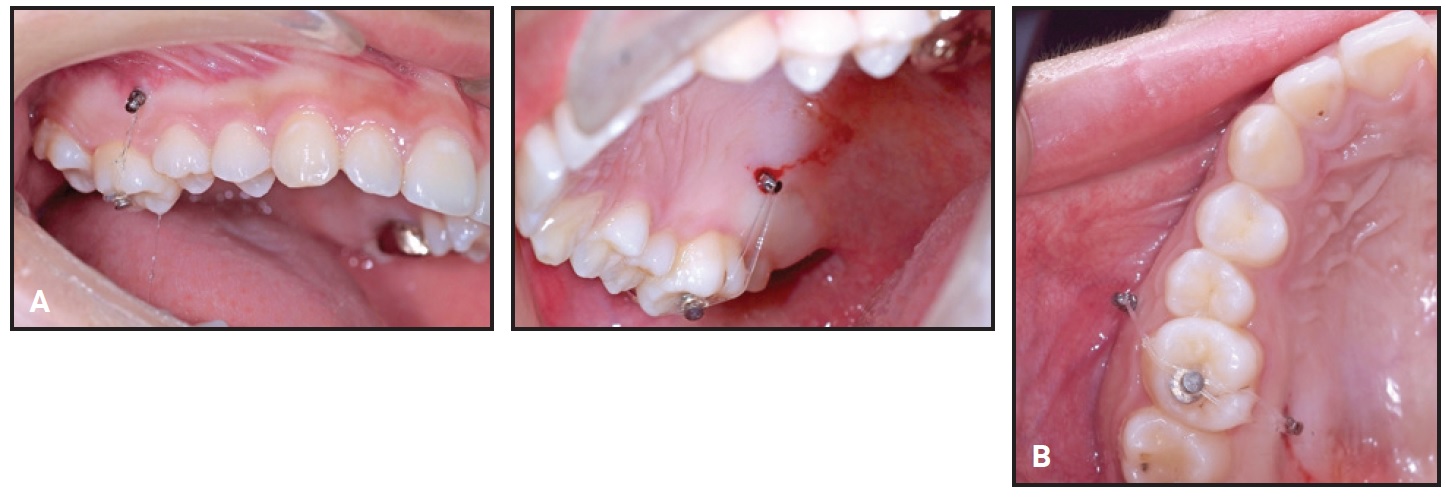

A 15-year-old female presented with a hopeless lower left first molar with periapical pathosis (Fig. 1).

Fig. 1 Case 1. 15-year-old female patient with hopeless lower left first molar before treatment.

She was referred for extraction of the first molar and protraction of the second and third molars to close the space. To minimize the risk of alveolar bone atrophy, the first molar was hemisected, and only the distal root was extracted before orthodontic mechanics were initiated.

Two small-headed, 6mm micro-implants* were placed into the buccal alveolar bone between the lower left first and second premolars (Fig. 2A). The micro-implants were tied together with stainless steel ligature wire and built up with composite resin. A standard .018" upper-incisor bracket was bonded to the composite (Fig. 2B), a tube was bonded to the lower second molar, and an .017" × .025" TMA** sectional wire was inserted to connect the bracket and tube.

Fig. 2 Case 1. A. Two micro-implants* placed between lower left first and second premolars and built up with composite. B. Bracket bonded to composite and connected to second-molar tube with TMA** sectional wire.